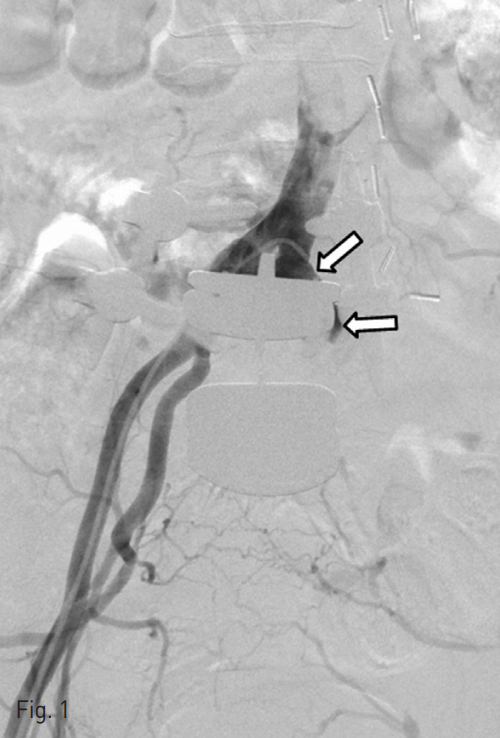

An angiography was attempted in order to localize a bleeding focus. It showed an occlusion of left common iliac artery (CIA) with a bulging contour at the occlusion site suggesting the presence of a pseudoaneurysm abutting the fixation metal of the lumbar vertebra (Fig. 1). The angiography was attempted via lumbar, right internal iliac and inferior mesenteric artery, and did not show a bleeding focus. The left renal artery stump at the left nephrectomy site was intact. A venogram via right femoral vein did not demonstrate abnormal communications. Hence, the angiography failed to identify a definite bleeding focus to account for gross hematuria.

Fig. 1

The angiography shows an occluded left CIA and a bulging vascular structure (arrows) behind the metal plate that is most likely to represent a pseudoaneurysm at the occlusion site